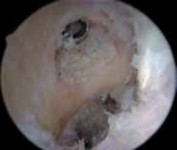

4. The previous graft is removed with a 5.5-mm shaver down to the footprint of the native ACL.

1. The shaver also is used to remove any fat pad obstructing the view, periosteum off the lateral wall of the notch, and any scar tissue present in the notch.

5. In revision ACL reconstruction, the notch often is overgrown and narrow, likely as a result of the previous ACL reconstruction (

TECH FIG 1A

).

1. A notchplasty is completed with use of a 5.5-mm burr, starting at the anterior opening of the notch if necessary.

2. The location of the previous femoral tunnel is noted.

3. Notchplasty is carried back to the posterior wall as needed. A small, curved curette may be used to inspect the back of the notch. A thin white strip of periosteum usually identifies the posterior wall (

TECH

### FIG 1B). Careful attention to localizing the posterior wall is critical, especially because the sides and roof of the notch often are irregular owing to the previous surgery.

1. Anterior placement of the femoral tunnel is the primary cause of recurrent laxity for ACL reconstructions, so in many cases there is enough room to place a second femoral tunnel in the appropriate position without interference or compromise from the previous tunnel. If this is the case, the previous interference screw can be left in place or removed (

TECH FIG 1C,D

A B C D E

TECH FIG 1 • A. Significant overgrowth of the notch noted at the time of revision anterior cruciate ligament (ACL) reconstruction. B. A thin layer of periosteum is easily visualized at the posterior wall of the notch. C. Note the anterior placement of the femoral tunnel interference screw used during the primary ACL reconstruction. The femoral tunnel for the revision can be placed at the appropriate location without removing the interference screw used in the primary procedure. D. The new femoral tunnel and interference screw are placed in the appropriate location without compromise from the screw used in the index procedure. E. View of femoral notch after placement of femoral tunnel and interference screw via anteromedial portal. This allows divergence of the old and new femoral tunnels.